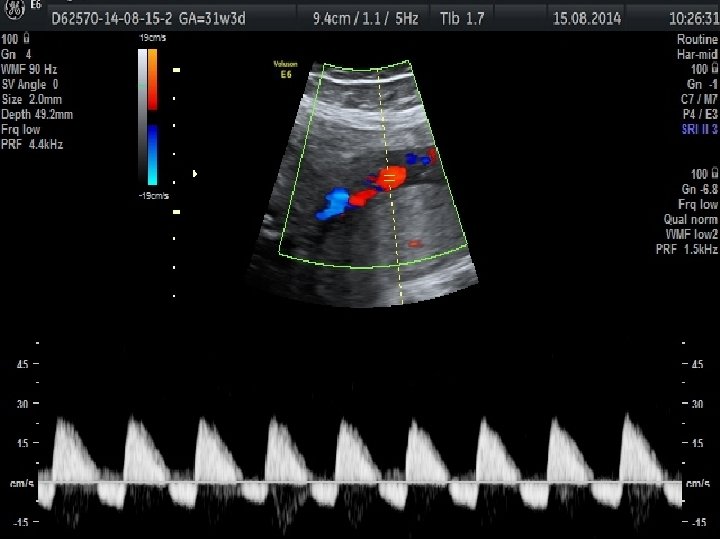

Obstetrik Doppler Ultrasonografi • Umblikal arter Doppler’i en yaygın olarak kullanılan fetal Doppler değerlendirmesidir ve en fazla kullanılan Doppler parametresidir. • Orta serberal arter Doppler • Umblikal arter Doppler değerlendirmesinde direnç artışı, diyastol sonu akımda kayıp veya ters dönme saptanması , artmış perinatal mortalite hızı ile ilişkili olmakla birlikte fetal gelişme geriliği olgularında doğum zamanlamasının belirlenmesini de etkilemektedir.

• Duktus venosus Doppler’inin kötü perinatal sonuçları tahmin etmedeki katkısı sınırlı olmakla birlikte yenidoğan sonuçlarını öngörmede en önemli kardiyovasküler parametre duktus venosus Doppler’idir.

Eğer akım transdu sere doğru ise, yol uzunluğu kısadır ve geri dönen frekans yu ksektir. Eğer akım transdu serden uzaklaşıyorsa, yol uzar ve geri dönen frekans azalır.